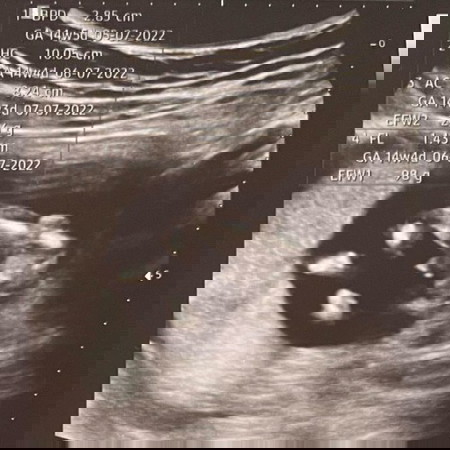

บ้านไหนรู้เพศแล้วบ้างค่ะ🥰 ดูออกกันไหม⁉️

14w ป้าหมอลงไปทางผู้ชายจ้า